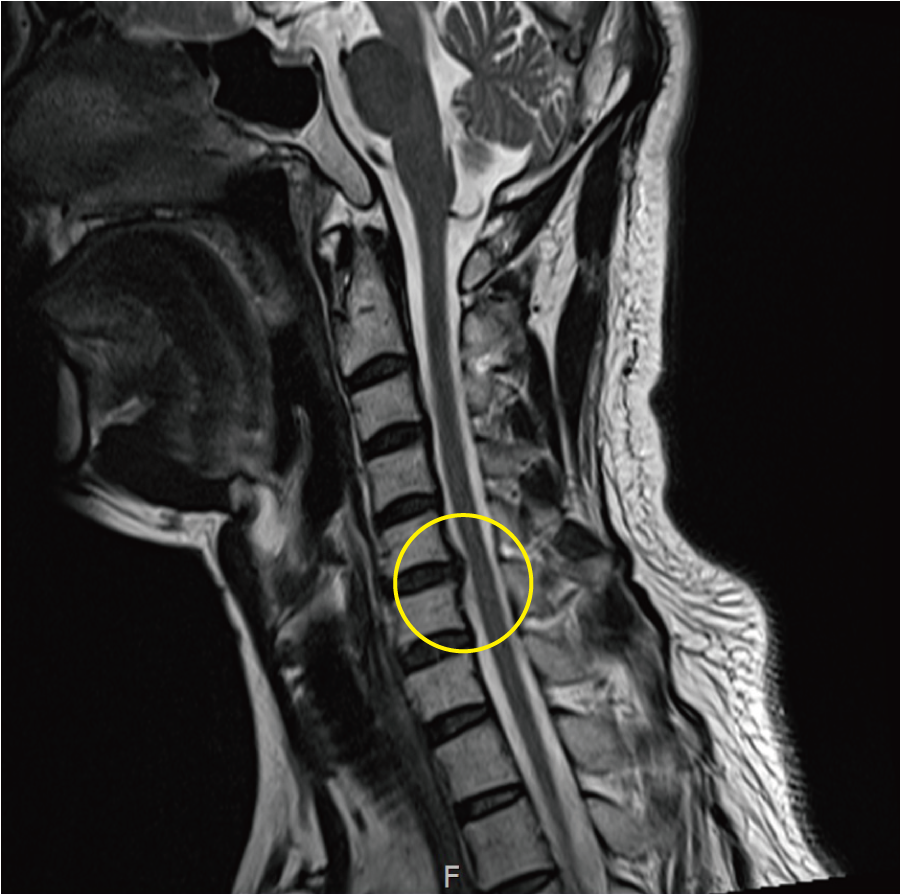

목디스크를 치료하기 위함으로는 다른 것과 비교하면도 전문 병원에서의 현재 추세에 대한 정확한 진단이 필요하죠. 위에서 설명드렸다시피 본인이 어떠한 사유로 인한 목디스크 증상을 앓고 있는지에 대하여도 체크가 필요하고, 나아가 현재 디스크가 경추 사이에서 탈출되면서 대략적으로로 신경 부위를 압박하고 있는지 그 수위에 대한 체크도 아주 중요해요.

비수술치료로 증상이 나아지지 않게 된다면 아니면 보존요양에도 되려 증상이 너무해진다면 다른 치료방법을 찾아야하는데 이 때는 마비에 대한 위험성이 높아지고 MRI상 신경 고장이 같이 함께다가오게되는 경우 수술치료 방식을 권유받게 돼요.